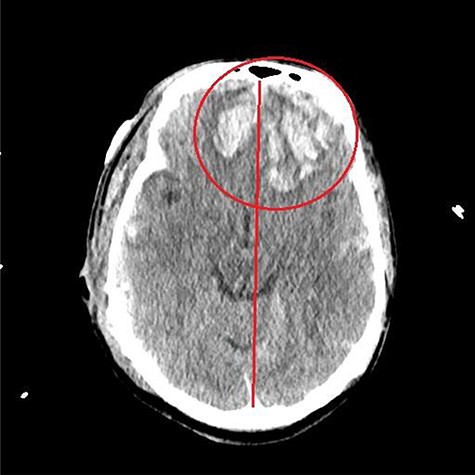

He was paralyzed, intubated and taken emergently to the OR due to nonresponsive hypovolemic shock. A right frontal ICP monitor was placed in the operating room while he was undergoing an emergency thoracotomy. Intraoperative ICP was in the 40s, and thus the patient was taken directly from the operating room to CT scan which showed enlargement of bilateral contusions, left greater than right, for which he was taken emergently to the operating room for a left hemicraniectomy (Figs 2 and 3).

CT head post thoracotomy with expansion of contusion with shift.